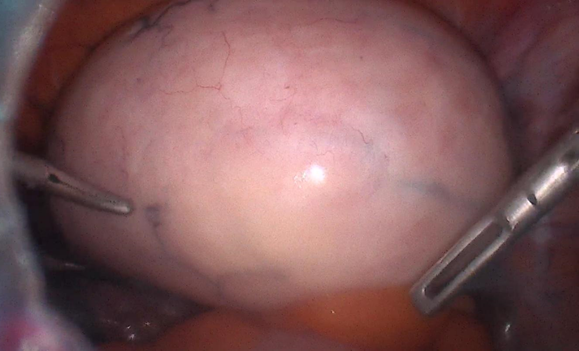

Intraoperative images

1. Intraoperative image visualized as right ovarian fibroma.

1. Right ovarian fibrothecoma, with dilated and elongated infundibulopelvic ligament.

1. There is evidence of a twist in the ipsilateral tube.